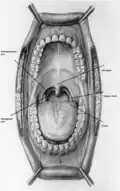

The oropharynx, at the back of the mouth, forms a circle and includes the base of the tongue (posterior third) below, the tonsils on each side, and the soft palate above, together with the walls of the pharynx, including the anterior epiglottis, epiglottic valleculae and branchial cleft at its base. The oropharynx is one of three divisions of the interior of the pharynx based on their relation to adjacent structures (nasal pharynx (nasopharynx), oral pharynx (oropharynx) and laryngeal pharynx (laryngopharynx – also referred to as the hypopharynx), from top to bottom). The pharynx is a semicircular fibromuscular tube joining the nasal cavities above to the larynx (voice box) and oesophagus (gullet), below, where the larynx is situated in front of the oesophagus.[31]

The oropharynx lies between the mouth (oral cavity) in the front and the laryngopharynx below, which separates it from the larynx. The upper limit of the oropharynx is marked by the soft palate and its lower limit by the epiglottis and root of the tongue. The oropharynx communicates with the mouth, in front through what is known as the oropharyngeal isthmus, or isthmus of the fauces. The isthmus (i.e., connection) is formed above by the soft palate, below by the posterior third of the tongue, and at the sides by the palatoglossal arches. The posterior third of the tongue or tongue base contains numerous follicles of lymphatic tissue that form the lingual tonsils. Adjacent to the tongue base, the lingual surface of the epiglottis, which curves forward, is attached to the tongue by median and lateral glossoepiglottic folds. The folds form small troughs known as the epiglottic valleculae. The lateral walls are marked by two vertical pillars on each side, the pillars of the fauces, or palatoglossal arches. More properly they are separately named the palatoglossal arch anteriorly and the palatopharyngeal arch posteriorly. The anterior arch is named from the palatoglossal muscle within, running from the soft palate to the tongue (glossus), while the posterior arch similarly contains the palatopharyngeal muscle running from the soft palate to the lateral pharynx. Between the arches lies a triangular space, the tonsillar fossa in which lies the palatine tonsil, another lymphoid organ. [32]

The external pharyngeal walls, consisting of the four constrictor muscles, form part of the mechanism of swallowing. The microscopic anatomy is composed of four layers, from the lumen outwards, the mucosa, submucosa, muscles, and the fibrosa, or fibrous layer. The mucosa consists of stratified squamous epithelium, which is generally non-keratinised, except when exposed to chronic irritants such as tobacco smoke. The submucosa contains aggregates of lymphoid tissue.[32][33]